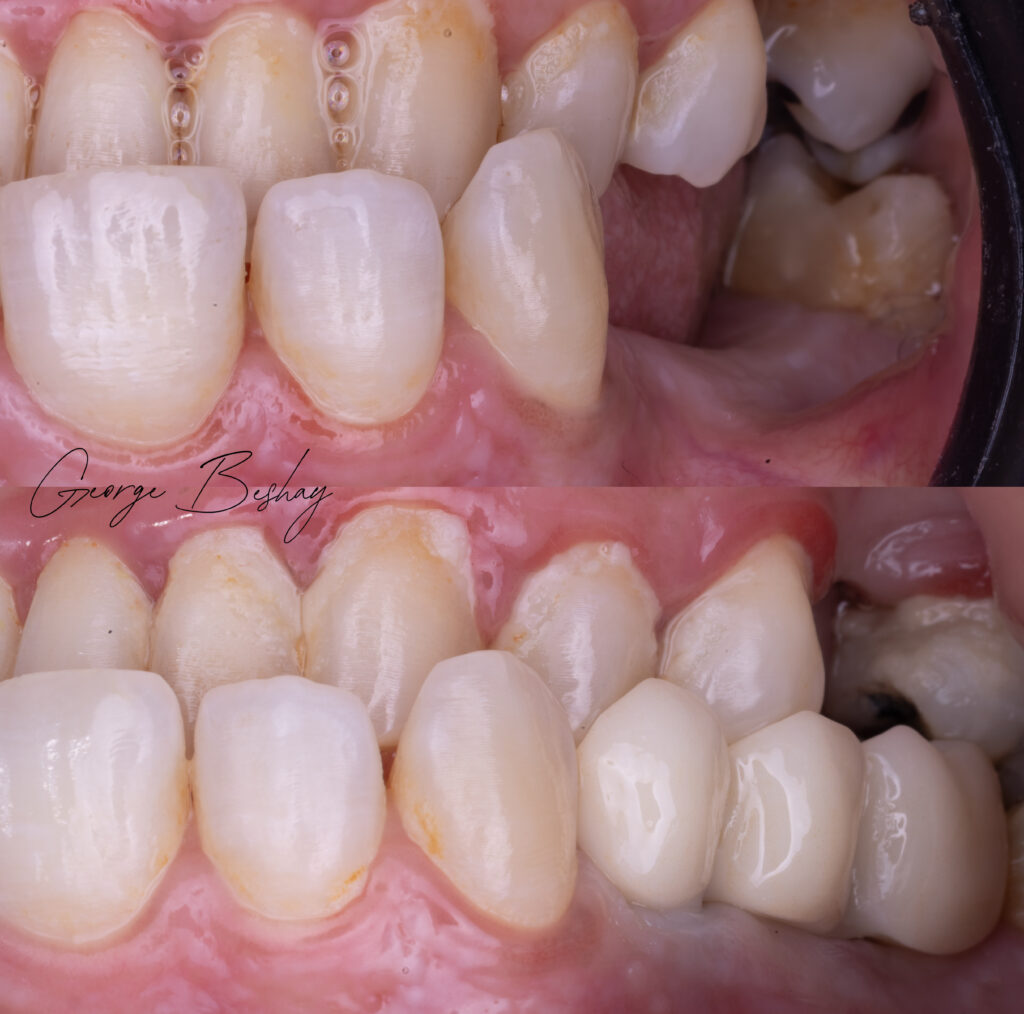

We placed a tilted implant, engaging available native bone, and restored the case with angled MUAs and a carefully planned distal cantilever to restore the molar.

Less invasiveness.

Shorter treatment time.

Not because we avoided complexity —

but because we respected biomechanics and prosthetic principles.